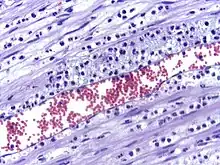

La perméabilité accrue des vaisseaux sanguins entraîne une exsudation (fuite) de liquide dans les tissus. La fuite de liquide provoque une augmentation de la viscosité du sang, ce qui augmente la concentration des globules rouges (congestion veineuse).

Les leucocytes engloutissent les microbes et les détruisent, générant la production de pus. Le pus sera éliminé vers l'extérieur si la lésion est en contact avec l'extérieur, ou il générera un abcès si la zone où s'est formé le pus est à l'intérieur d'un organe.